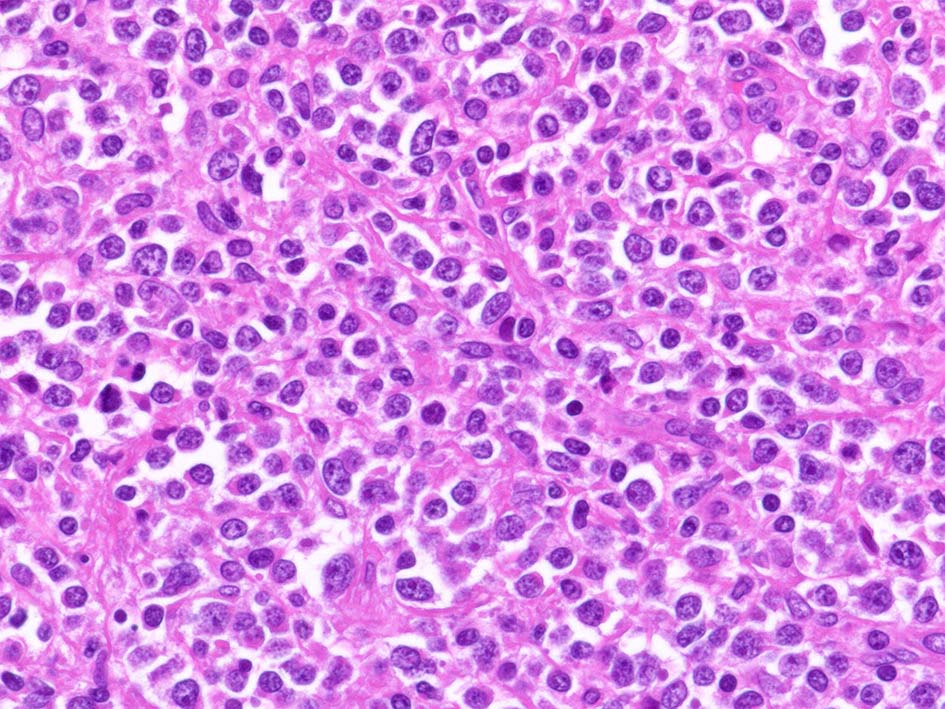

小リンパ球と同程度か1.5倍くらいのサイズ, round/ convoluted nucleiをもつリンパ球がシート状密に増殖する. 核クロマチンは粗で, 核小体が認められる核もある.

DLBCLとは細胞の大きさや細胞所見が異なっている. 精細管への浸潤, 占拠所見がある.